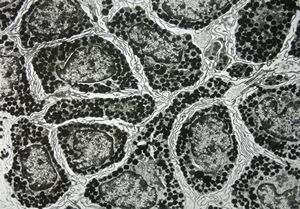

M, 12y. | urticaria pigmentosa

F, 1y. | urticaria pigmentosa

F, 1y. | urticaria pigmentosa

M, 13y. | mast cell

F, 6y. | urticaria pigmentosa